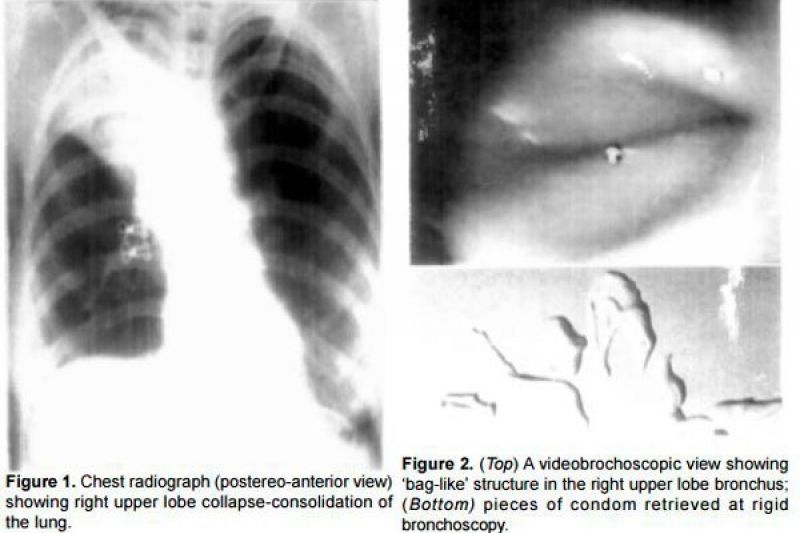

Quando os sintomas não desapareceram, os médicos resolveram realizar uma broncoscopia e descobriram a presença de uma estrutura presa aos brônquios, um preservativo masculino. O objeto foi facilmente removido com uma pinça de biópsia, mas se rasgou em pedaços durante o procedimento.

A paciente, uma professora de 27 anos, por seis meses lidou com uma tosse persistente, que estava acompanhada de alguns sintomas de pneumonia. A princípio, os exames iniciais não mostraram discrepâncias, porém, quando foram feitas radiografias do tórax, descobriram uma lesão no pulmão. Logo, ela fora medicada com um coquetel de tratamento para tuberculose.